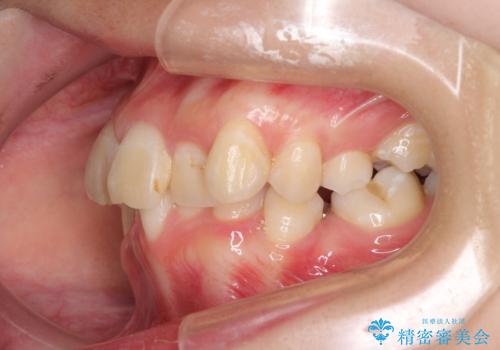

デコボコと深い咬み合わせ ワイヤー装置での抜歯矯正

- 内側に倒れ込んだ歯や下の前歯が隠れてしまうほどの咬み合わせを改善したいとのことで来院された患者様です。

下顎の叢生を解消するために抜歯が必要であり、奥歯の咬み合わせや口元の印象から、上顎も同様に抜歯と判断し、上下左右の第1小臼歯4本抜歯してワイヤー装置にて矯正治療を行うこととしました。